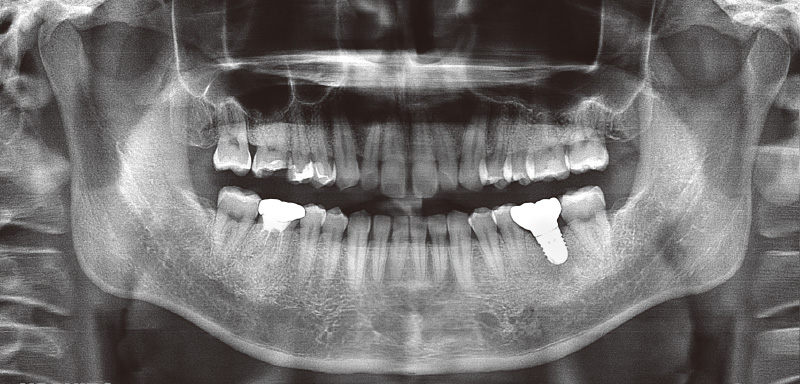

48歳男性、初診:2024年9月12日

主訴:左下の奥歯で噛めるようになりたい(図6, 7)。

₆、₇にインプラントを埋入し左側の咬合を得る治療計画を立案。φ4.5長さ9.5mmのSPIイニセルインプラント エレメントRCを埋入した(図8)。まずはここで初期固定を得られたのでヒーリングキャップにて封鎖した(図9)。今回は勤務医たちへの指導の意味もあり、ガイデッドサージェリーにて行った。そして4週目でクローズドトレーにてシリコン印象を行い補綴装置をセットした(図10,11)。CBCT撮影を行い骨レベルの状態を確認し、機能的審美的にも問題ないことがわかっている(図12, 13)。

![[写真] 初診時のパノラマX線写真(2024年9月12日)](/academic/dentalmagazine/wp-content/uploads/sites/2/2025/09/194-8_photo07.jpg)

図7 初診時のパノラマX線写真(2024年9月12日) -

![[写真] インプラント埋入後のパノラマX線写真(2024年9月28日)](/academic/dentalmagazine/wp-content/uploads/sites/2/2025/09/194-8_photo08.jpg)

図8 インプラント埋入後のパノラマX線写真(2024年9月28日) -

![[写真] 補綴装置セット後のパノラマX線写真(2024年11月4日)](/academic/dentalmagazine/wp-content/uploads/sites/2/2025/09/194-8_photo10.jpg)

図10 補綴装置セット後のパノラマX線写真(2024年11月4日) -